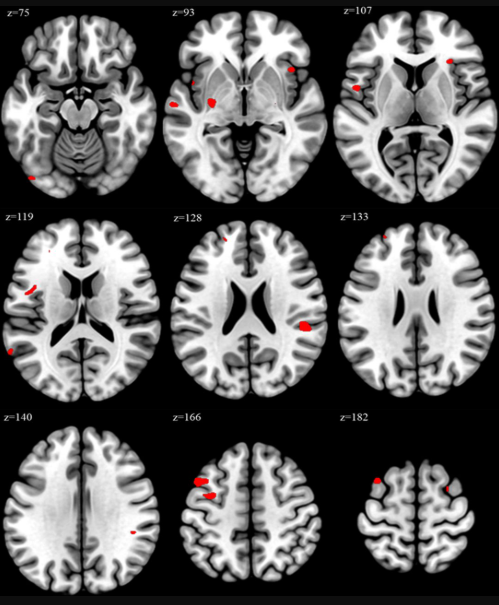

Differences in brain volume were assessed using voxel-based morphometry (VBM)---a neuroimaging technique that identifies and compares regional differences in levels of grey matter-and atlas-based analysis, which uses pre-defined references to identify and label structures in images like brain scans.

VBM showed that people who worked 52 or more hours a week displayed peak increases in 17 regions, including the middle frontal gyrus, the superior frontal gyrus (which is involved in attention, planning, language processing and decision-making), and the insula, when compared to participants who worked standard hours every week. The insula has a key role in integrating sensory, motor, and autonomic feedback from the body. It is involved in emotional processing, self-awareness, and understanding social context.